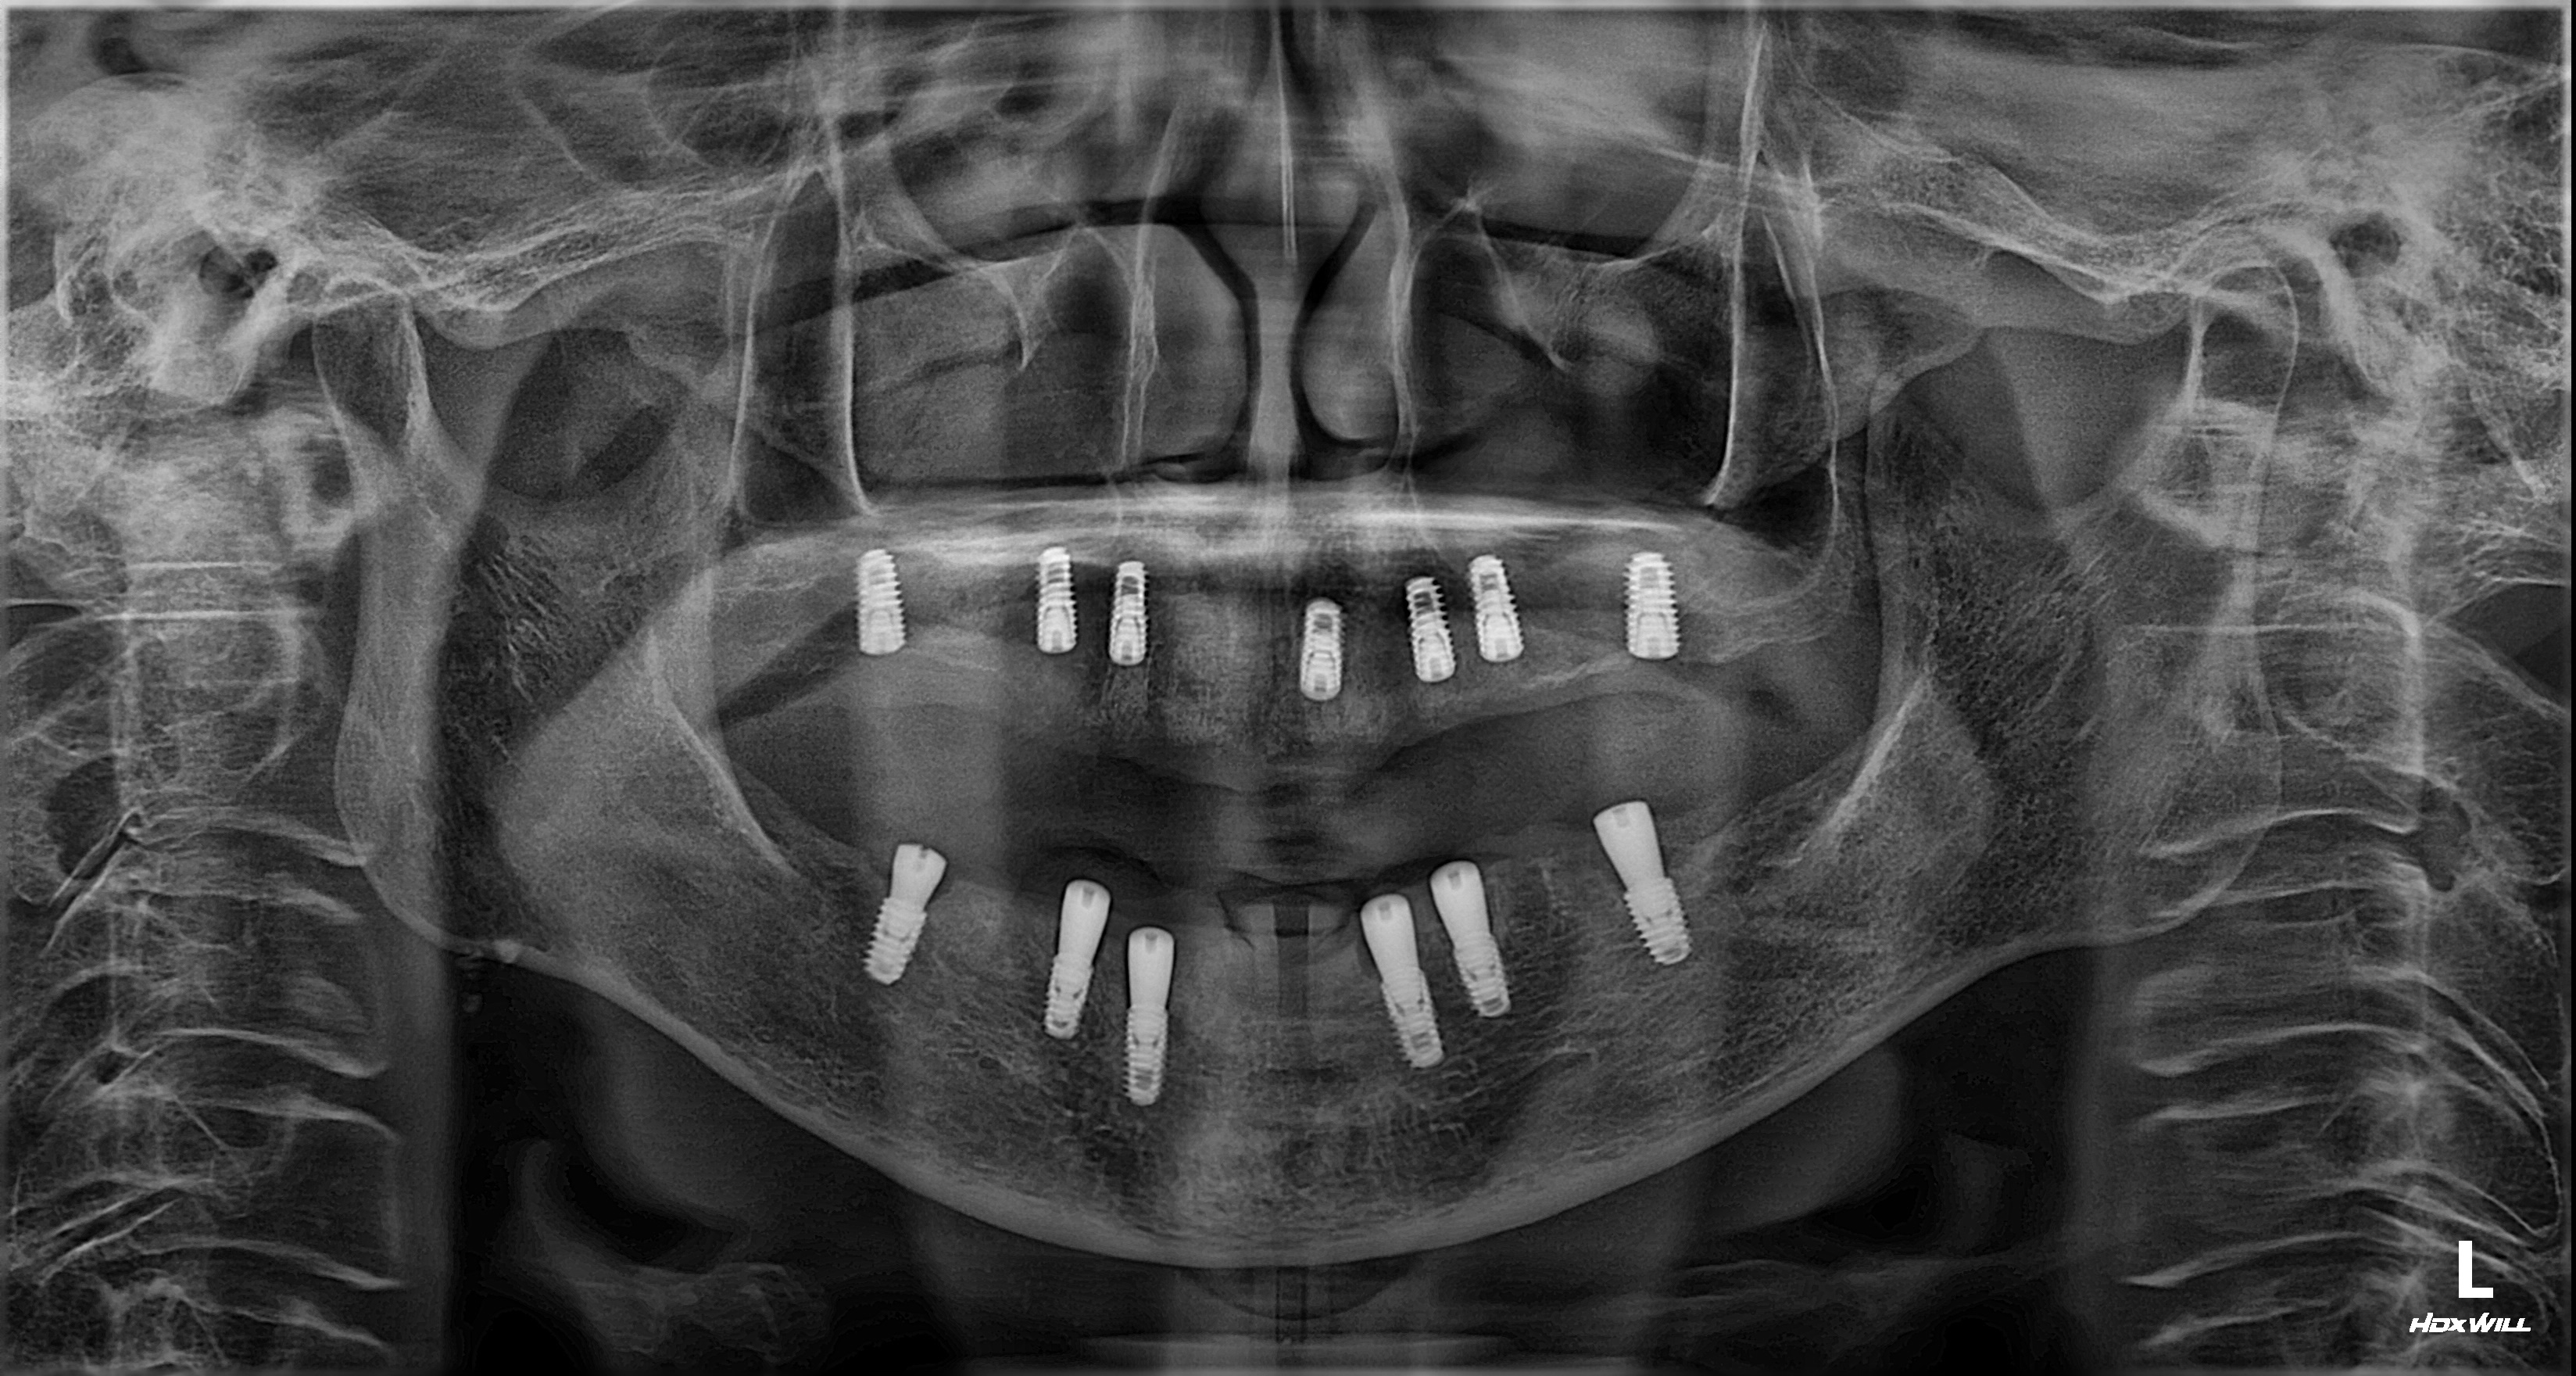

촬영일시: 2025.12.31 [ 치료기간: 2025년 06월 05일 ~2025년 12월 31일 ] ※ 365서울앞선치과의원의 모든 컬럼은 각 진료과 의료진이 직접 작성합니다. 365서울앞선치과의원 임상 케이스 게시물은 환자분께 의학적으로 정확하고 상세한 정보를 드리기 위해 각 진료과 의료진이 직접 작성하며, 모든 증례 사진은 본원 의료진이 직접 시술한 증례를 촬영한 것으로, 의료법 제23조, 제56조에 의거하며 환자분의 동의를 얻어 포스팅에 사용하였습니다. 또한 해당 케이스는 본 환자분의 치료 결과이며, 환자 상태에 따라 치료의 결과는 달라질 수 있습니다. |